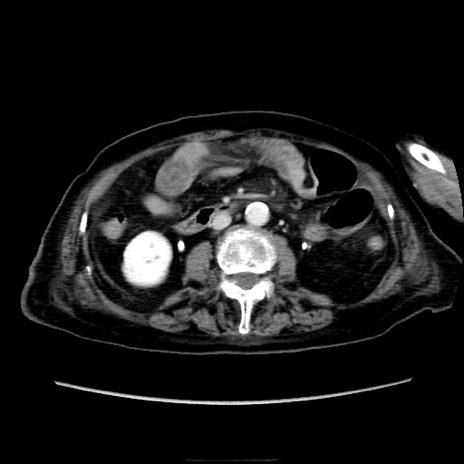

症例40(横断像)

【症例】90歳代女性

【主訴】腹痛・嘔吐

【現病歴】 食欲低下、嘔吐があり昨日他院受診。肺炎と診断され入院となる。入院後より腹部全体に圧痛あり。胃管留置され経過みていたが、症状持続するため、

当院転院となる。

【既往歴】胸椎圧迫骨折、胆石症

【身体所見】腹部:中央に激痛あり、圧痛あり、反跳痛不明

【データ】WBC 17100、CRP 18.82

他院CT

横断像